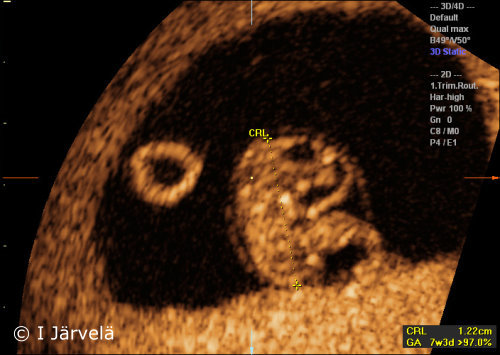

Pregnancy Week 7 (Ultrasound Scan)

Pregnancy week 7 (ultrasound scan). The amnion lining around the fetus is visible in the 7th week of pregnancy. The yolk sac remains outside the amniotic cavity.

Picture: Ilkka Järvelä; text: Dimitrios Scordas